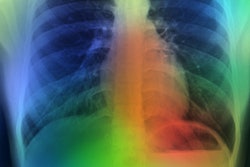

(Left) Area with fracture (in the box). This may not be easily picked up by an inexperienced radiographer. (Right) An AI-generated heatmap, directing the radiographer to check the area. Figure courtesy of Clare Rainey and MURA dataset.The survey highlights issues with the perceptions of reporting radiographers in the U.K. regarding the use of AI for image interpretation, according to Rainey.